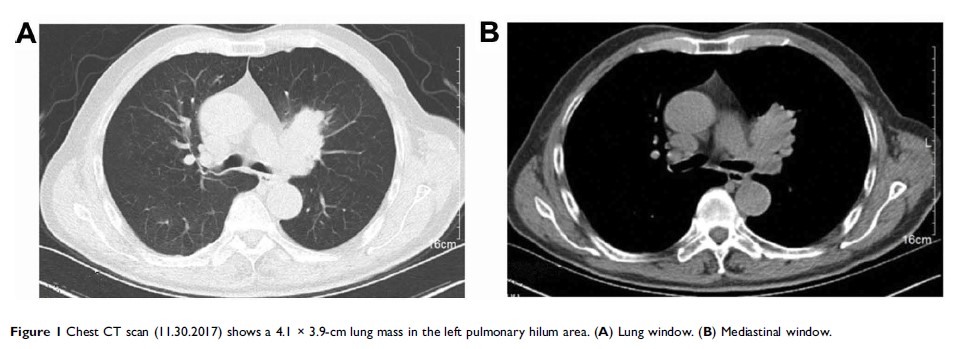

罕见的同步多发性肺癌:鳞状细胞癌和小细胞肺癌